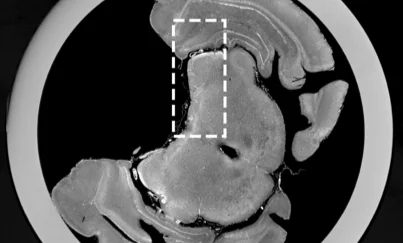

Dark-field CT monitoring of tissue freezing

Multimodal monitoring of dynamic processes, by adding phase-contrast and dark-field channels to conventional CT for enhanced contrast and quantitative information. One example: tracking tissue cryoablation as it happens.

Fig. from Sci. Rep. 14, 5599 (2024) · CC-BY